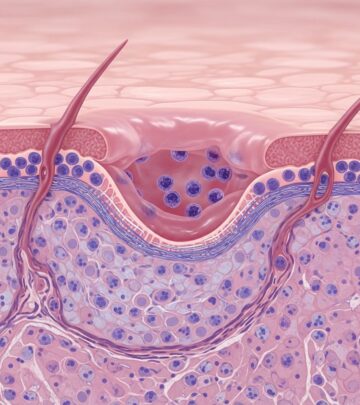

Fibrofolliculomas in Birt-Hogg-Dubé Syndrome Images